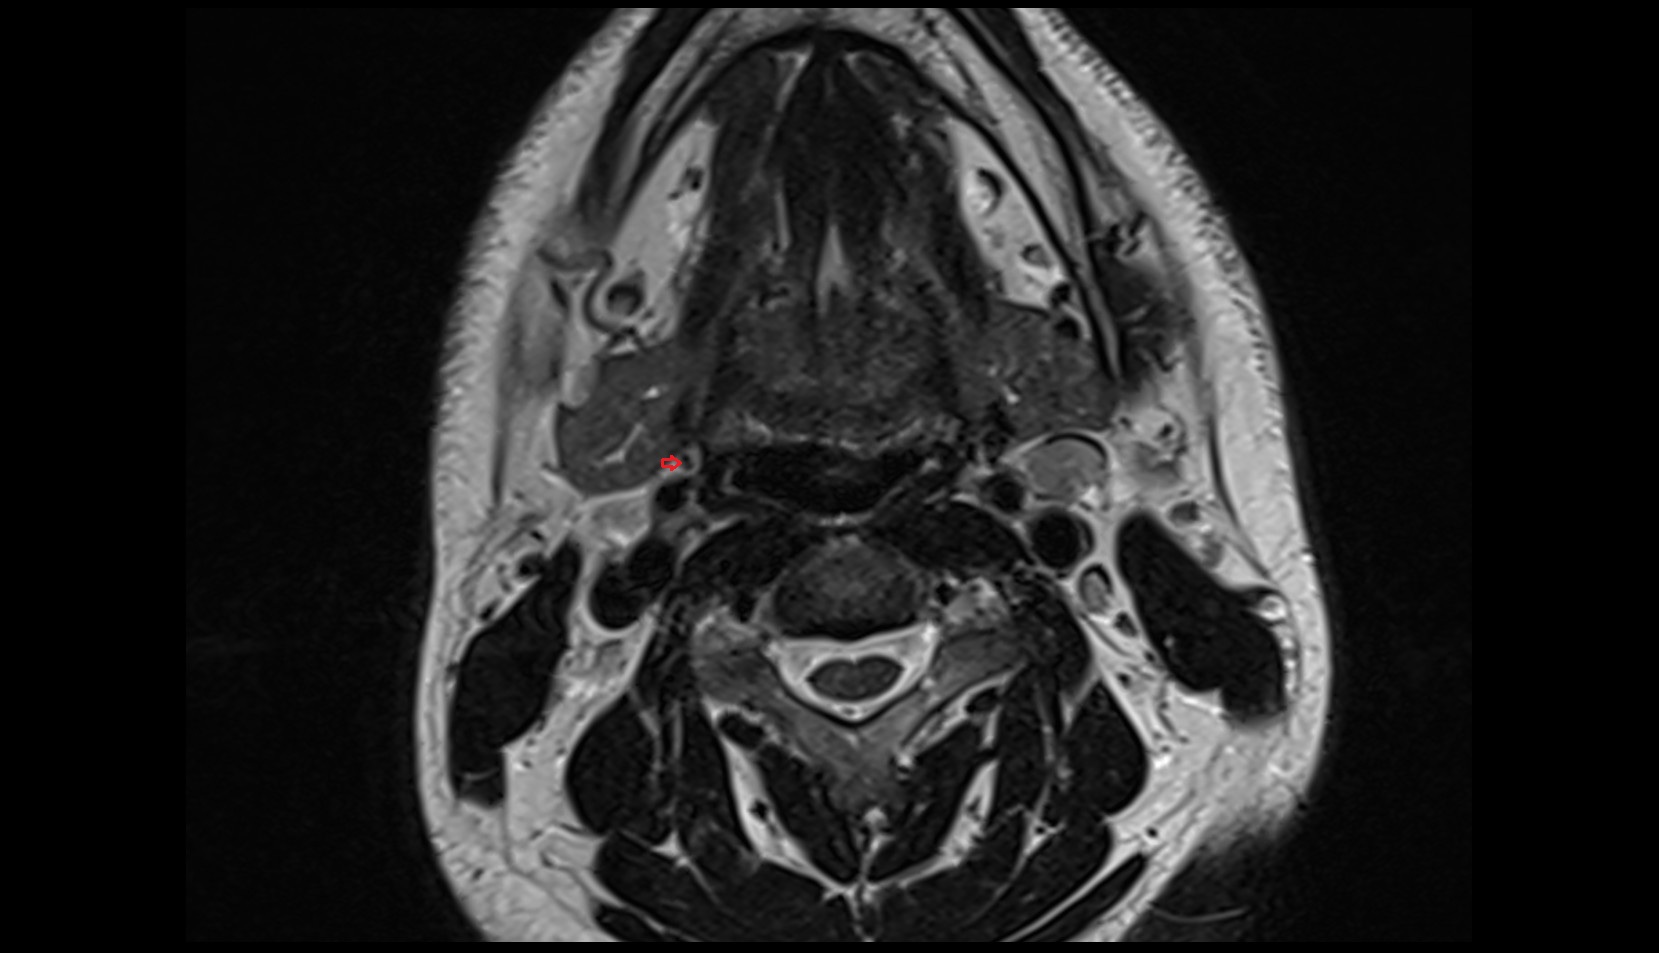

- Temporomandibular joint

- Mandibular condyle

- Mandibular fossa

- Mastoid process

- Petrous part of temporal bone

- Squamous part of temporal bone

- Zygomatic process of temporal bone

- Deep part of masseter muscle

- Superficial part of masseter

- Superior head of lateral pterygoid muscle

- Inferior head of lateral pterygoid muscle

- Lateral pterygoid muscle

- Masseter muscle

- Medial pterygoid muscle

- Temporalis muscle